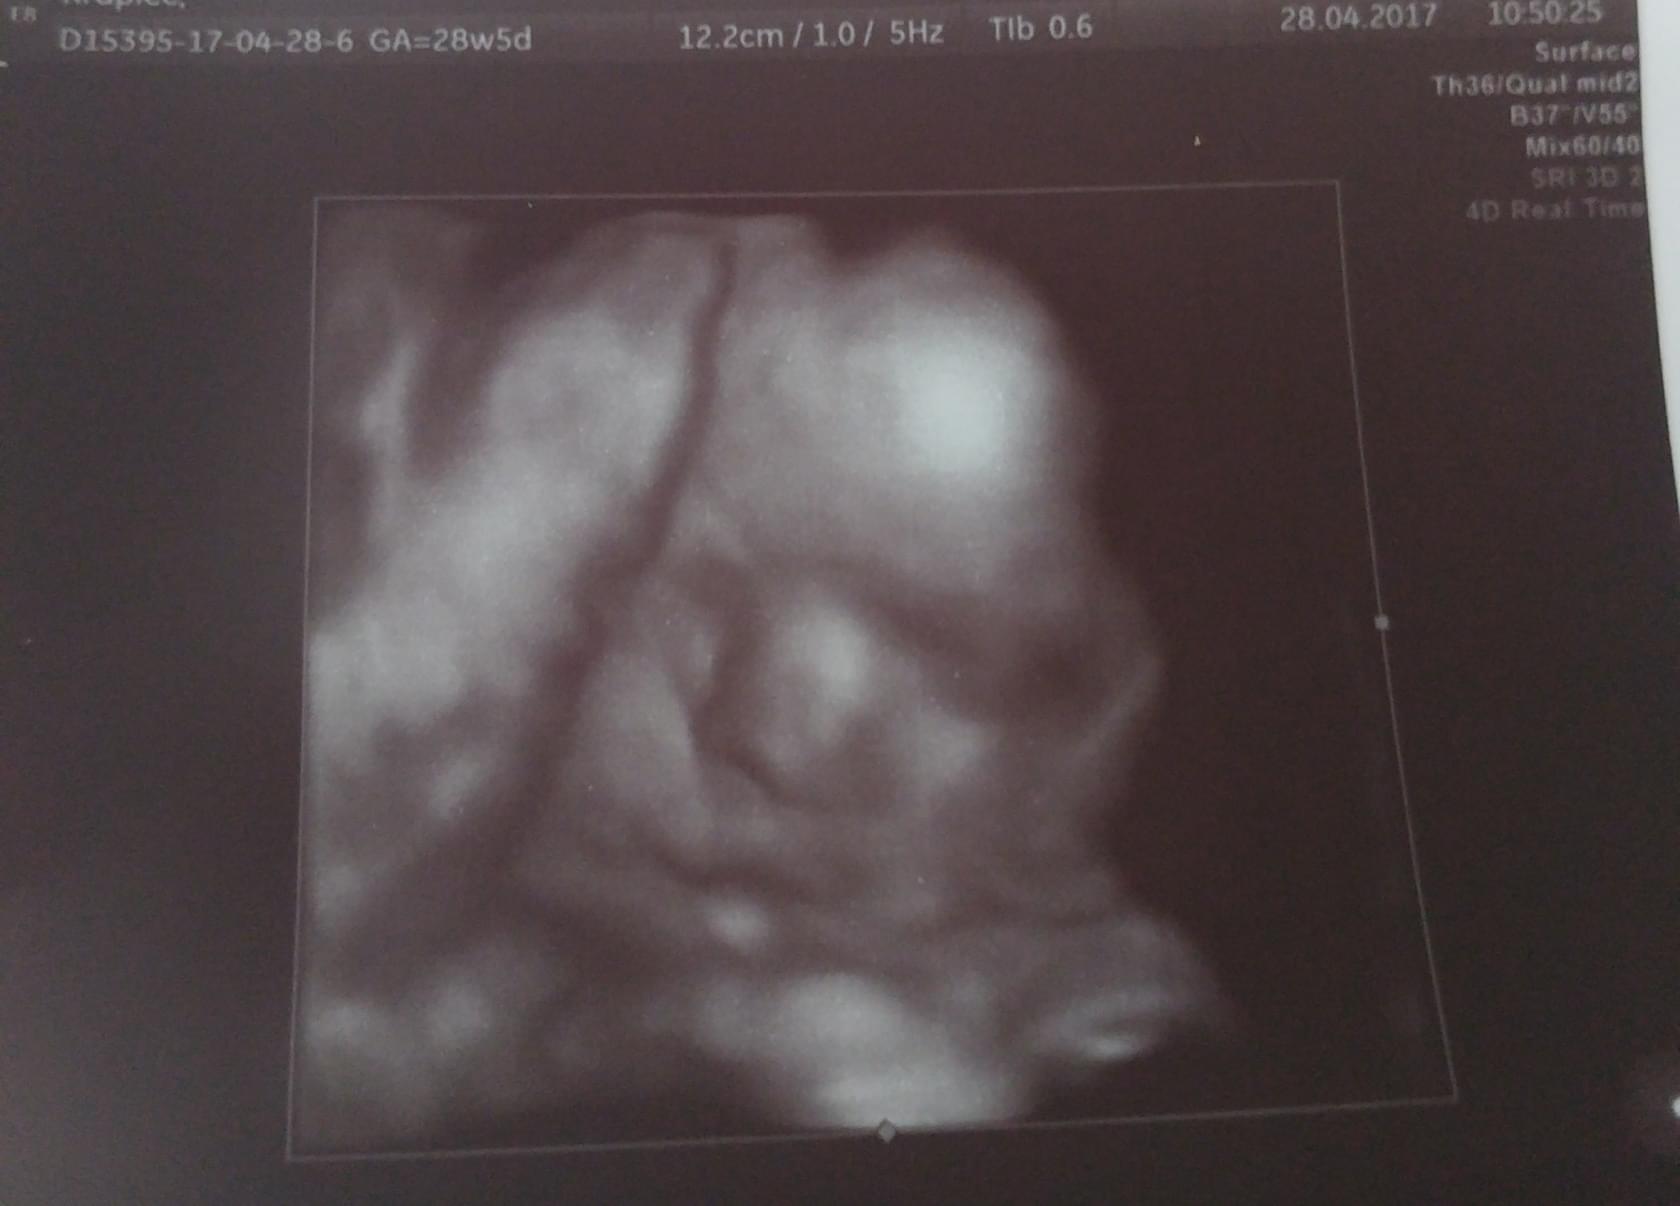

Napisalam na fb więc i tutaj napisze

Niki wazy 1148g

bryka i szaleje, wszystko ma na swoim miejscu. Lekarka stwierdziła, że ma owsiki

bo się wierci i wierci. Ale ładnie buzię pokazała

nic nie przytyłam od ostatniej wizyty o_O i wizyty już co 3 tygodnie